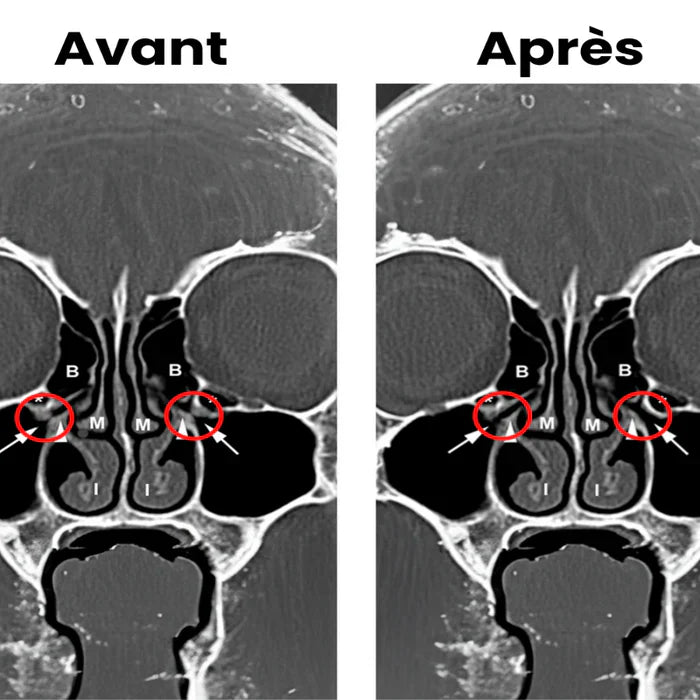

Tecnologia clinicamente testata

Vitalora by Pureliss" utilizza una lunghezza d'onda ottimizzata per penetrare in profondità nella mucosa nasale e stimolare la circolazione sanguigna. Questo riduce il gonfiore e migliora il drenaggio nasale, fornendo un sollievo rapido ed efficace. Clinicamente testato e raccomandato dagli esperti, è una soluzione sicura e naturale per migliorare il benessere delle vie respiratorie.